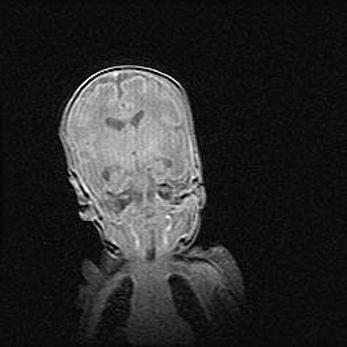

Подострая гематома правой гемисферы мозжечка.

Наружная гидроцефалия.

Возраст: 15 дней

Вес: 3100 г

Пол: женский

Окружность головы: 37 см

Срок гестации: 35-36 недель

При открытой наружной форме гидроцефалии у новорожденных расширяются и переполняются субарахноидные пространства.

Кровоизлияния в мозжечок имеют две клинико-анатомические формы: полушарные гематомы и кровоизлияния в червь.

К появлению этой патологии может привести: повреждения головного мозга, возникающие в результате асфиксии и гипоксии плода при беременности, или травмы во время родов. Редко гематома мозжечка может быть результатом первичной коагулопатии и сосудистой мальформации, диссеминированном внутрисосудистом свертывании, изоиммунной тромбоцитопении.